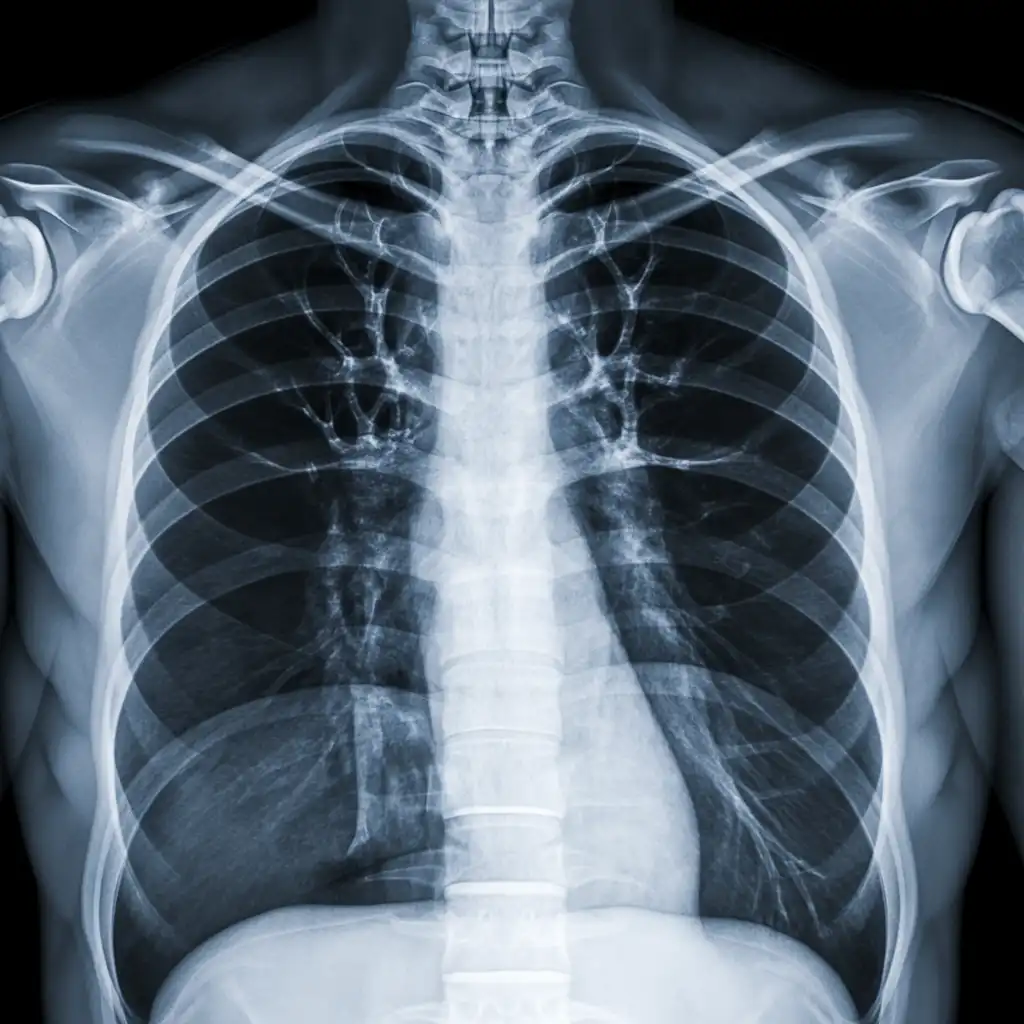

Una radiografia a domicilio è un esame radiologico eseguito da un tecnico specializzato che viene a casa tua con apparecchiature digitali portatili. L’esame si svolge sul posto, senza spostare il paziente e con la stessa qualità di una struttura ospedaliera.

Dopo l’acquisizione delle immagini, queste vengono inviate al medico radiologo che referta rapidamente e ti invia tutto in formato digitale. Un servizio comodo, sicuro e ideale per chi ha difficoltà negli spostamenti.